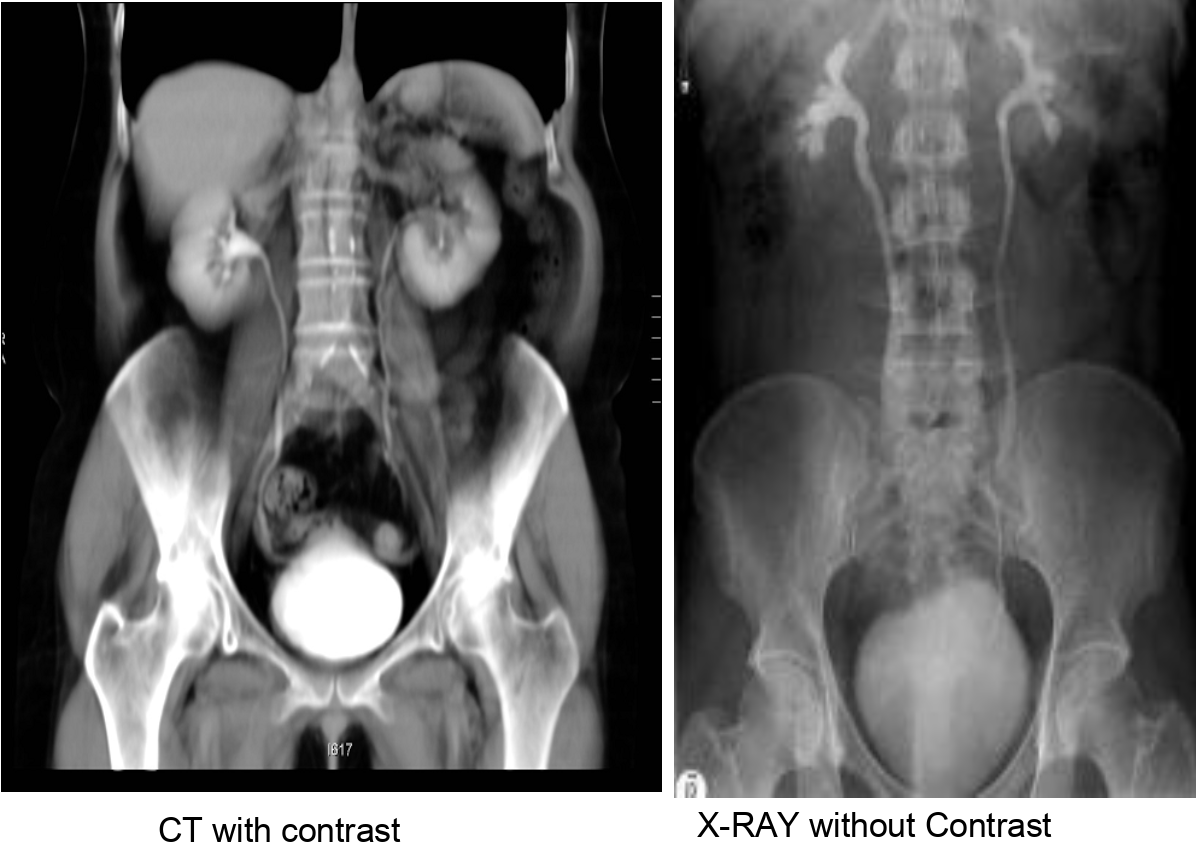

Urography, urethrocystography, and excretion urography

Visualization of the urinary tract after administration of radiopaque contrast medium (containing iodine).

Intravenous injection of contrast media: excretory urogram.

Intravenous pyelography